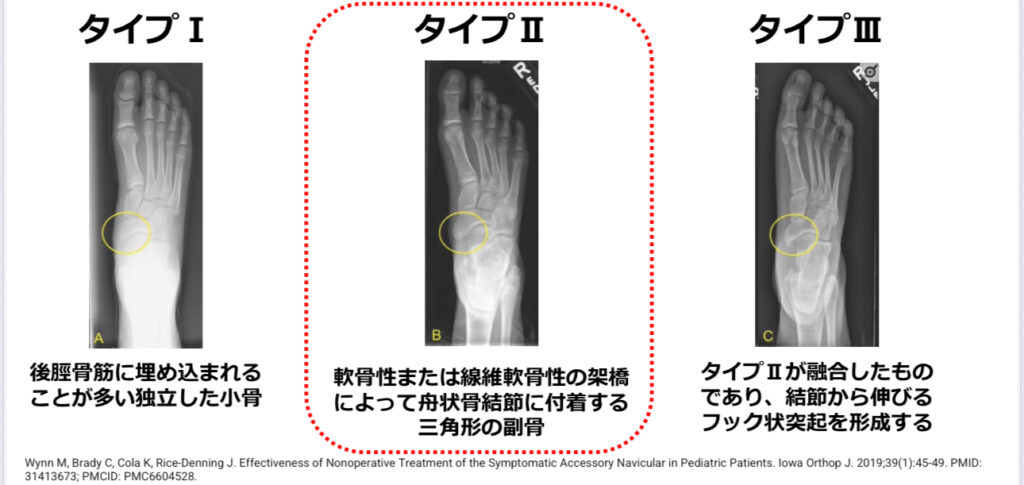

有痛性外脛骨のタイプ